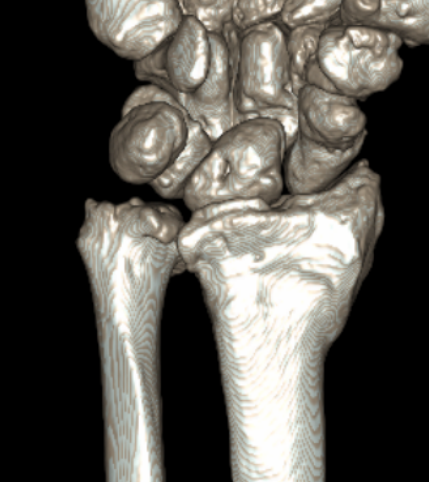

CT guided 3D planning

- RCT of 40 patients with radial malunion

- 2D versus 3D planning and patient specific surgical guides

- 3 degree better correction in 3D group

- non significant trend towards better outcomes in 3D group